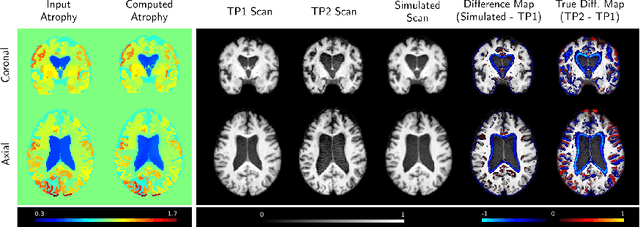

Abstract:We present a proof-of-concept, deep learning (DL) based, differentiable biomechanical model of realistic brain deformations. Using prescribed maps of local atrophy and growth as input, the network learns to deform images according to a Neo-Hookean model of tissue deformation. The tool is validated using longitudinal brain atrophy data from the Alzheimer's Disease Neuroimaging Initiative (ADNI) dataset, and we demonstrate that the trained model is capable of rapidly simulating new brain deformations with minimal residuals. This method has the potential to be used in data augmentation or for the exploration of different causal hypotheses reflecting brain growth and atrophy.